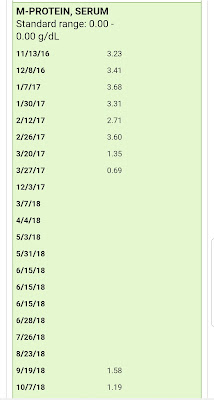

I just can't believe that 9 years ago this time Myeloma was RAGING inside of me, and I didn't know it yet.... My IGA was close to 5800 (normal = 70-400). My M Protein was over 4.3 (normal = 0) and my first Bone Marrow Biopsy showed 70% cancerous myeloma plasma cells! And here I am to talk about it, almost 9 years later, having survived more rounds chemo than I can count, a Stem Cell Transplant, and all the 9 years of side effects I have endured! But I'll reminisce about all of this soon...

2- Next I agreed to begin the Vintage chemo Cytoxan with my Velcade and Dex steroids... only I am going to Cheat... ssshhhh don't tell my Dr yet, but no way am I downing 8 frikn Cytoxan pills at one time! I asked her for a lower dose, and she was kind enough to lower the standard of 10 Cytoxan pills to 8, but after I picked up the Rx, and saw them, and began to visualize ingesting all of them at once!... I'm Helllllllooooo, Noooooo, I'm not going to put all those in me at once, risking a nasty GI backlash! I know, I know, I'm a Cancer Patient with Incurable High Risk Myeloma, and I should be on board for high dose- kill off those super strong myeloma cells trying to kill me!! Well, yes, but No! At this point in my life, and treatment.... Quality of Life, and lessening the chance of feeling gross and sick, is my main priority! Yes my myeloma is 4 Times the High End of Normal right now... but sorry, I just can't stand the idea of getting grossly GI sick. See way baaaaaack in June 2010 I had "that reaction" to IV Cytoxan, and uuggghhhh, nope, no thank you... not again, if possible. So Tomorrow Night, Oct 29, after taking 40mg Dex steroids in the morning, my weekly Velcade shot in the afternoon, I will very tentatively, unbravely take 4, yes four of the 8 Cytoxan pills!

I'm also armed with Zofran, but I don't think I'll "pregrame" with that just yet, as I'll be on the high dose, 40mg Dex steroids, and that should help with any nausea, right?? Suggestions please!!!, if you've done this combo, which most of the Myeloma patients have, early on! Why didn't I?? I was concerned about all the warnings from myeloma patients about BAD Neuropathy from Velcade, so I skipped over to Kyprolis, and never had the Cytoxan pills added in, as Kyprolis Dex worked for me for about 10 months, then Darzalex, Pomalyst, Dex worked for me for about 18 months, so here I am, going backwards to meds I skipped, before I'll do clinical trials, CAR T, etc. Yes, no matter how "bad" my situation becomes, Quality of Life is first and foremost to me... since what's the point of treating myeloma, if I'm so sick all the time, I'm not living. Isn't the point of treatment to give a cancer patient their life back??? I've been doing this for almost 9 years now, and for so many hours, days, weeks, months, etc, my life has been so limited by side effects, I learned that for me, the treatment has to make sense... kill the cancer cells, but let me see the sunshine too!